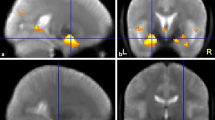

A complete review of memory fMRI functioning for adult TD populations is beyond the scope of the current review (for review, see Rugg and Vilberg, [39]). Rugg and Vilberg [39] review two of the main types of memory fMRI paradigms employed that dissociate recollection and familiarity. One uses the “Remember/Know” procedure, where participants report whether recognition of an item is accompanied (Remember) or unaccompanied (Know) by retrieval of contextual details during studying. The other requires a judgment about contextual features during studying (a “source memory” judgment, e.g., color of font). In sum, recollection-sensitive fMRI effects have been found in the hippocampus, parahippocampal, retrosplenial/posterior cingulate, lateral parietal cortices, and mPFC. There is evidence from adult TD studies that activity in the hippocampus increases when retrieval is associated with conscious recollection of a learning episode, and not when items are recognized only by familiarity or unrecognized [40] (see Fig. 1). Further, fMRI provides evidence for material specificity, such that each hippocampus is specialized to process specific types of information in TD adults; with verbal encoding resulting in left lateralization [41, 42] and visual encoding in right [41] (see Fig. 2).

Results from hippocampal region of interest, comparing correct R and correct K response amplitudes (a). Event-related responses within the left hippocampal region; response amplitude for correct R trials was greater than that for correct K trials (b). Adapted with permission from Eldridge et al. [40]